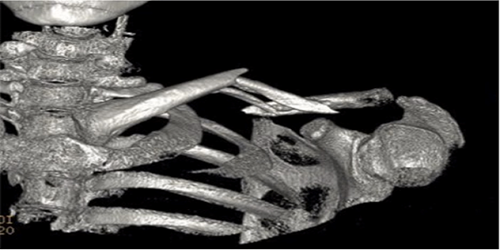

b) Broken upper end of humerus (arm) bone.

This injury becomes more common as we get older, so skiers above the age of 40 are more likely to suffer this problem.  A direct blow onto a shoulder can break the upper end of the bone.  This is the region where your rotator cuff tendons insert onto your arm bone and where the joint surface of the ball rests. Patients often develop bruising in their upper arm and chest and it is very sore. Occasionally there can be numbness in the upper arm.  If you have fallen and are worried about your shoulder you can usually access an X-ray at a clinic in resort and this will tell you whether you have a break.  If you have broken your shoulder and your skin is intact and the ball is in joint, then a simple sling will make it safe for you to return to the UK. Do seek an Orthopaedic surgeon’s advice on your return: while many of these injuries can be treated without surgery, some patients will do better with early surgery to fix or replace the damaged parts. You may require a CT scan (special X-rays that generate a 3D image of your injury) to help your surgeon give you the best advice about the need for surgery.